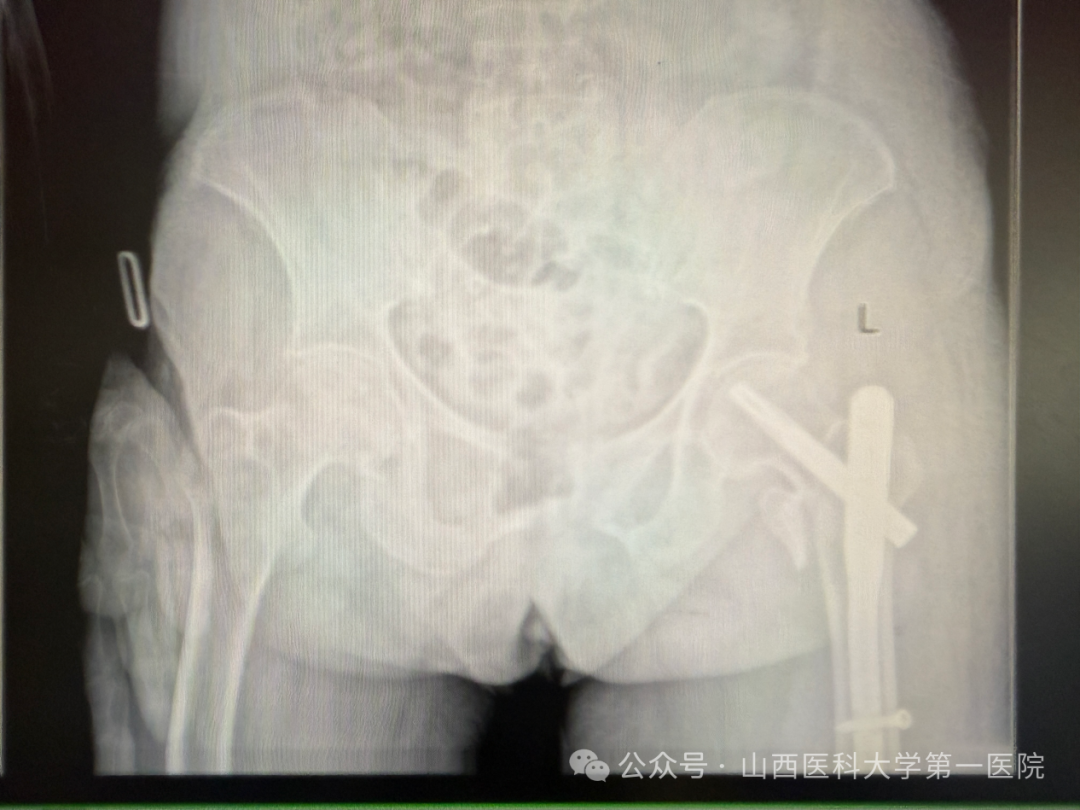

手术当日,杨自权主任团队借助丰富的手术经验,术前在牵引床、G臂辅助下迅速给予患者闭合复位骨折断端,结合经典的“2-1-1”微创手术切口实施手术,手术过程顺利,G臂透视可见骨折复位满意,髓内钉位置满意。术后患者顺利出院,安返家中。